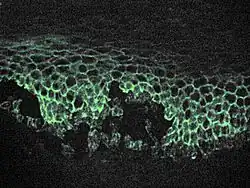

Pemphigus defines a group of autoimmune intraepithelial blistering diseases that are characterized by loss of normal cell-cell adhesion (acantholysis), and by the presence of pathogenic (predominantly IgG) autoantibodies reacting against epithelial adhesion molecules.[8] Pemphigus is further divided in two major subtypes: pemphigus vulgaris (PV) and pemphigus foliaceus (PF). However, several other disorders such as IgA pemphigus, IgE pemphigus, pemphigus herpetiformis, drug-induced pemphigus, Senear Usher syndrome, and endemic pemphigus foliaceus exist, and are recognized by a dermatologist from the appearance and distribution of the skin lesions. It is also commonly diagnosed by specialists practicing otolaryngology- head and neck surgery, periodontists, oral and maxillofacial surgeons, and eye doctors, as lesions can affect the eyes and mucous membranes of the oral cavity. Intraorally, it resembles the more common diseases lichen planus and mucous membrane pemphigoid.[13] Definitive diagnosis requires examination of a skin or mucous membrane biopsy by a dermatopathologist or oral pathologist. The skin biopsy is taken from the edge of a blister, prepared for histopathology and examined with a microscope. The pathologist looks for an intraepidermal vesicle caused by the breaking apart of epidermal cells (acantholysis). Thus, the superficial (upper) portion of the epidermis sloughs off, leaving the bottom layer of cells on the "floor" of the blister. This bottom layer of cells is said to have a "tombstone" appearance.

Definitive diagnosis also requires the demonstration of antidesmoglein autoantibodies by direct immunofluorescence on the skin biopsy. These antibodies appear as IgG deposits along the desmosomes between epidermal cells, a pattern reminiscent of chicken wire. Antidesmoglein antibodies can also be detected in a blood sample using the ELISA technique.